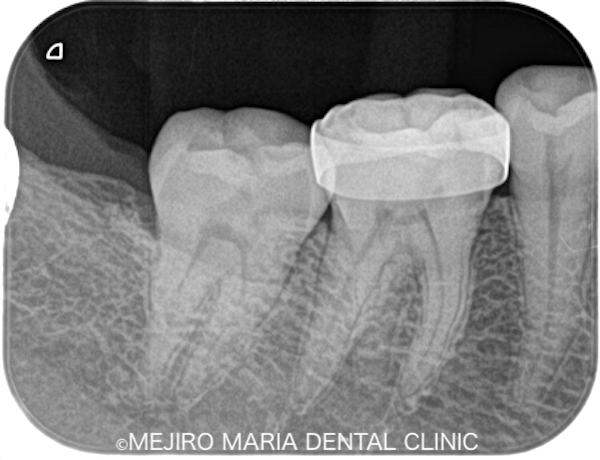

|治療前レントゲン画像6.png)

|治療後レントゲン画像7.png)

根管治療終了後、患者様が訴えていた痛みは10分の1程度まで消失し、現在は仮歯にて経過観察中です。

|治療前治療後画像-e1643198480907.jpg)